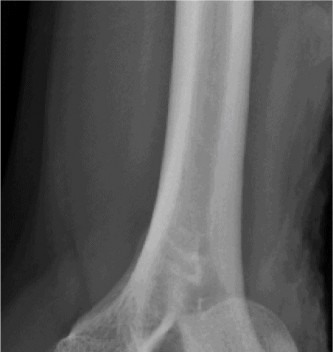

Plain Radiographs:

- Anteroposterior (AP) and lateral views of the elbow demonstrated a posteromedial dislocation of the ulna relative to the humerus.

- A significant fracture of the anteromedial coronoid process was clearly visible on the lateral view, displacing proximally.

- No obvious radial head fracture or olecranon fracture was identified on these initial views.

- The trochlea appeared to be displaced laterally relative to the coronoid fracture fragment.

Following initial radiographs, a closed reduction attempt was made in the emergency department under conscious sedation. The elbow was gently reduced, confirmed by post-reduction radiographs. However, despite reduction, the elbow remained grossly unstable, particularly with valgus stress and supination, demonstrating persistent posteromedial subluxation. This finding strongly suggested significant ligamentous and bony disruption.